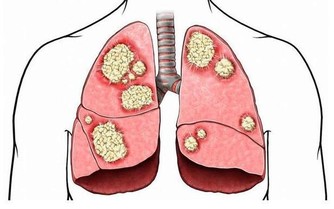

數據一:根據衛生福利部的公布,癌症時鐘快轉,每五分四十秒就有一人罹癌!

二○一一年全台罹癌人數新增了九萬二千多人,較前一年增加二.二%,創歷史新高。